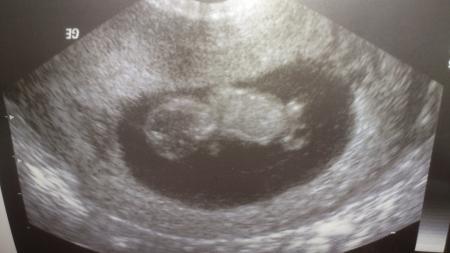

EInen wunderschönen guten morgen Ihr Lieben, Heute bin ich in der 11 SSW und ich hofe das in den nächsten Wochen das mit der übelkeit vorbei ist, und ich wieder ein bischen mehr auf die reihe bekomme. Dann habe ich heute endlich nach vier langen Wochen wieder Baby TV und ich bin mega gespannt darauf habe aber auch ein bischen Angst das nicht alles okay ist und ich bekomme heute meinen Mutterpass. Wünsche Euch einen schöne Stressfreie Woche

So es ist alles bestens die Ärztin ist zufrieden. Ich muss zwar zum Organ ultraschall in der 20 Woche und Fohlsäure mit mir soll ich nehmen ansonsten alles Super.

Bild zu

Süßes Bild!!!!! :)